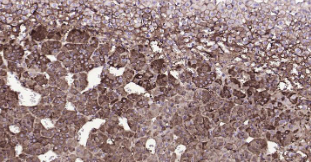

Immunohistochemical analysis of paraffin embedded rat adrenal gland tissue slide using IHC0220R (Rat Tyrosine Hydroxylase IHC Kit).